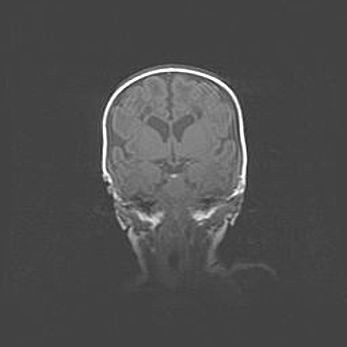

Церебральная ишемия II.

Возраст: 5 дней

Вес: 3400 г

Пол: женский

Окружность головы: 35 см

Срок гестации: 39 недель

Церебральная ишемия – это заболевание, характеризующееся недостаточностью (гипоксией) либо полным прекращением (аноксией) снабжения мозга кислородом по причине закупорки одного или нескольких сосудов. Это приводит к  что метаболическим расстройствам различной степени тяжести в тканях головного мозга, развитию коагуляционных некрозов и гибели нейронов.